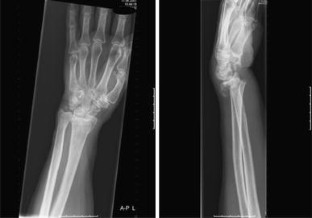

Fig. 4

Distal radius fractures are one of the most common fractures in the elderly females. In this article, we report a case of a distal radius fracture type AO-A3 with dorsal instability, in an older woman with manifest osteoporosis, treated with minimally invasive Cortoss® composite and FFS-wires®. A 63-year-old woman sustained an unstable distal radial fracture of her left wrist after falling from a kitchen step. She underwent an open reduction of the fracture and fixation with two crossed-fixation pins and Cortoss® composite. Post-operative plaster cast immobilization was given for 2 weeks, after which the plaster cast and the fixation pins were removed. At 4 weeks follow-up, she had a good functional result of her left wrist, after 11 months there was a complete return of grip strength with also, except for the palmar flexion, a full return of function. We report here the first case of a successful surgical treatment with Cortoss® composite of an AO-A3 type distal radius fracture.